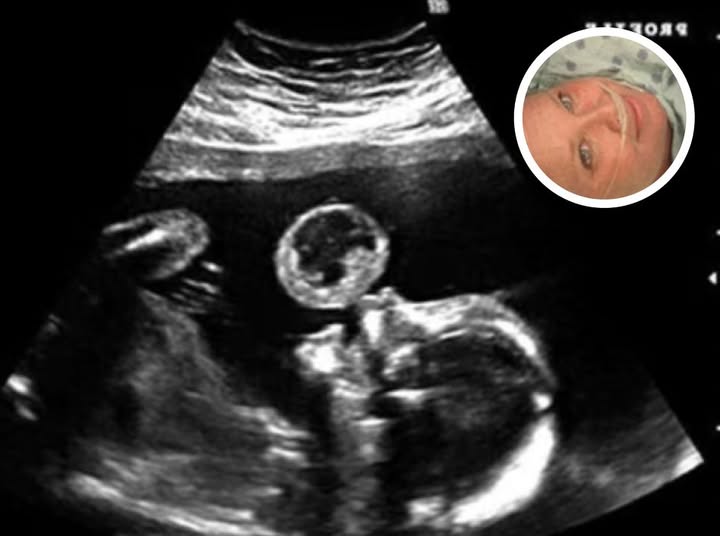

In the ultrasound image, right beside the baby’s tiny face, a perfectly round shape floated in the womb — something no one in the room could immediately explain. Emily remembers the sudden silence, the way the technician’s smile faded, and how the doctor stepped closer to the monitor with narrowed eyes.

Further scans revealed the truth: the “bubble” wasn’t a trick of the camera. It was a rare cystic growth forming right next to the baby — a condition so uncommon that most doctors go their entire careers without seeing it. If it continued to grow, it could block the baby’s airway at birth… or worse.

Today, Emily shares both the ultrasound photo and the first picture of Noah in the hospital — a reminder of the fear she faced, and the miracle that followed.